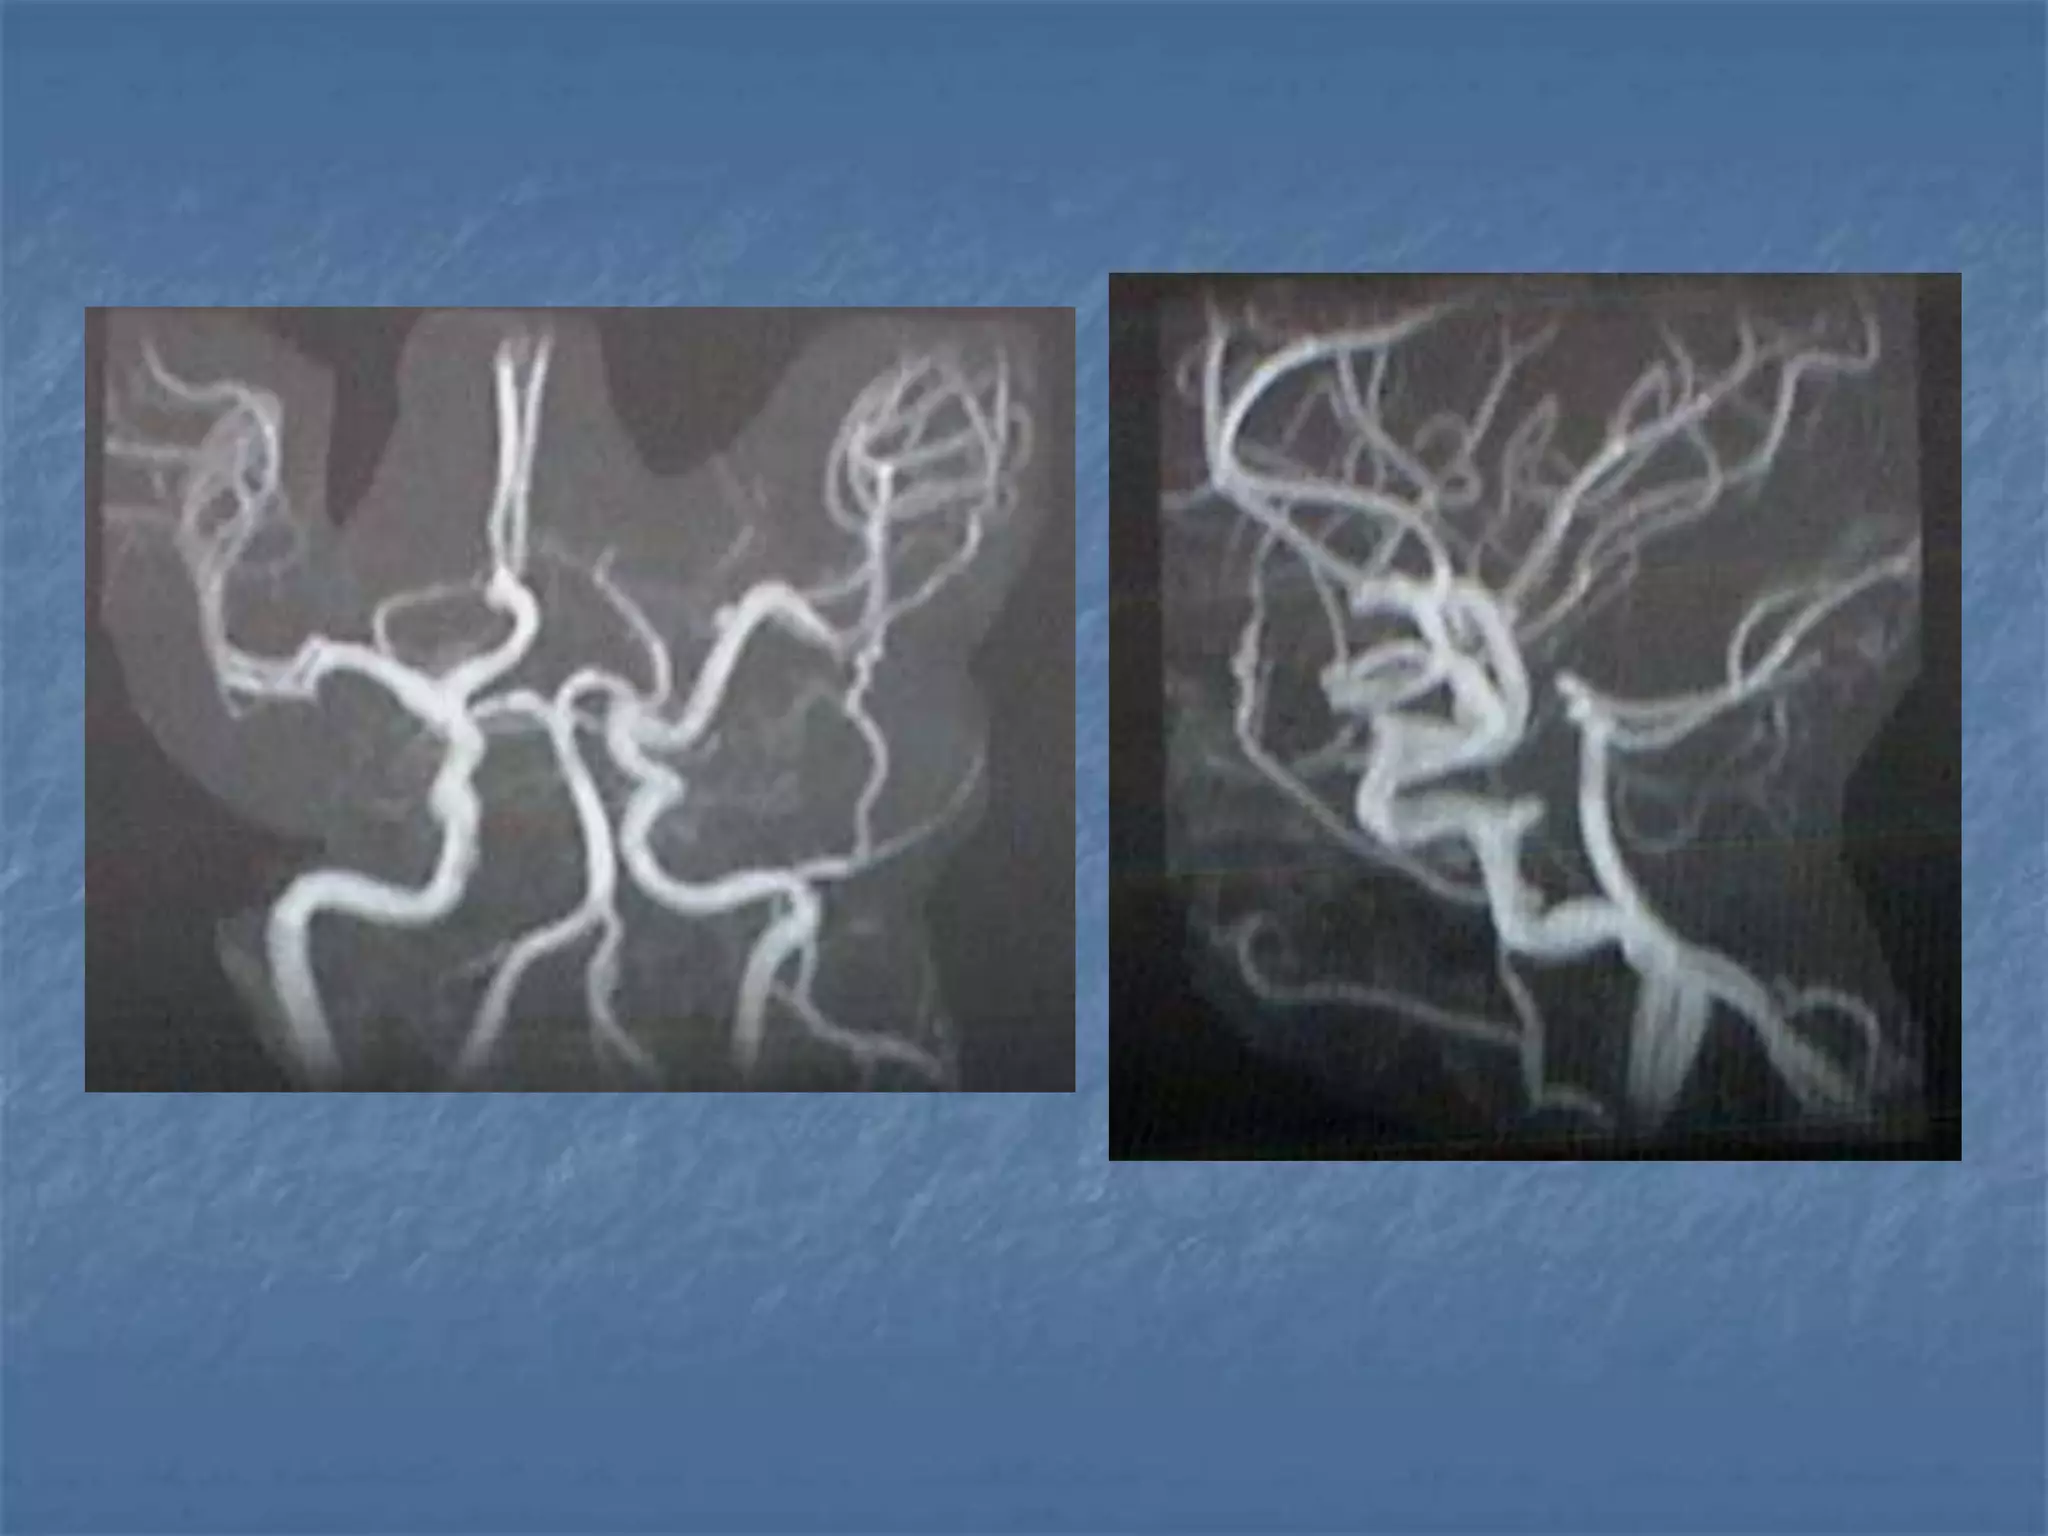

CT Angiography

 Site of occlusion

 Length of occluded

segment

 Arteries beyond occluded

segment – collateral flow

 Detection & exclusion of

large vessel intracranial

occlusion – sens – 98.4%

and spec.-98.1%

JCAT 2001; 25(4):520-8